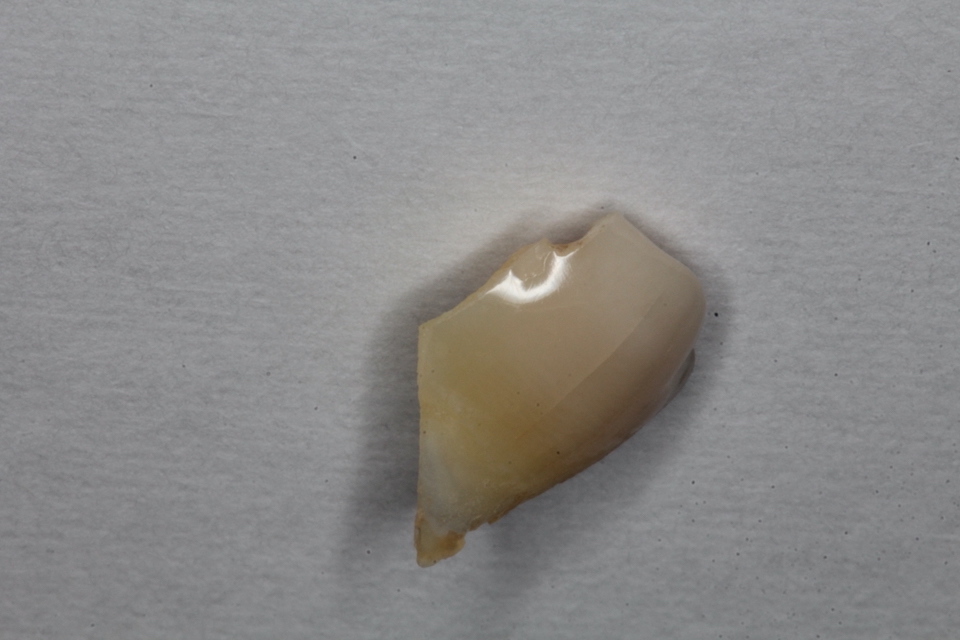

究極のワンオペ歯科治療シリーズ1.0

最近、歯科業界も少子高齢化で助手も歯科衛生士も不足気味、それに加えて不況で助手を雇うお金もないのか、人手不足と経費削減の為ワンオペ歯科治療をしよう!というセミナーまであるらしい。僕も歯科技工は外注せずになるべく口腔内で終わるべくワンオペでやっているので、それをシリーズ化してみようと思う。50代女性、左上6欠損この方なるべく削りたくないということで8年前、接着性義歯を作った。接着性の義歯というのは取り外しの義歯をスーパーボンドで接着するというもので、普通はないものです。これもワンオペ向きの治療法で歯科技工も口腔内での治療も難しくなく時間もかからない、患者にとってもメリットが大きいのでご紹介してみます。その時の画像2017/07/12奥の7番はハイブリッドCK、手前の5番はCRで再建している。ほとんど削っていない。金属は銀合金を使っている。酸化皮膜があるのでスーパーボンドの接着性が良い。強度もまあまあだ。何より柔らかいので研磨作業が楽だ。青のシリコンポイントだけで研磨できる。金属も安いし、これはワンオペにはありがたい。口腔内セット次回は8年後、つづく